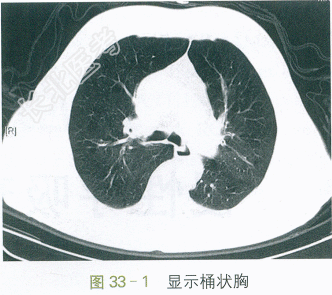

胸部平扫CT:肺气肿,两肺少量慢性为主炎症。如图33-1、图33-2所示。